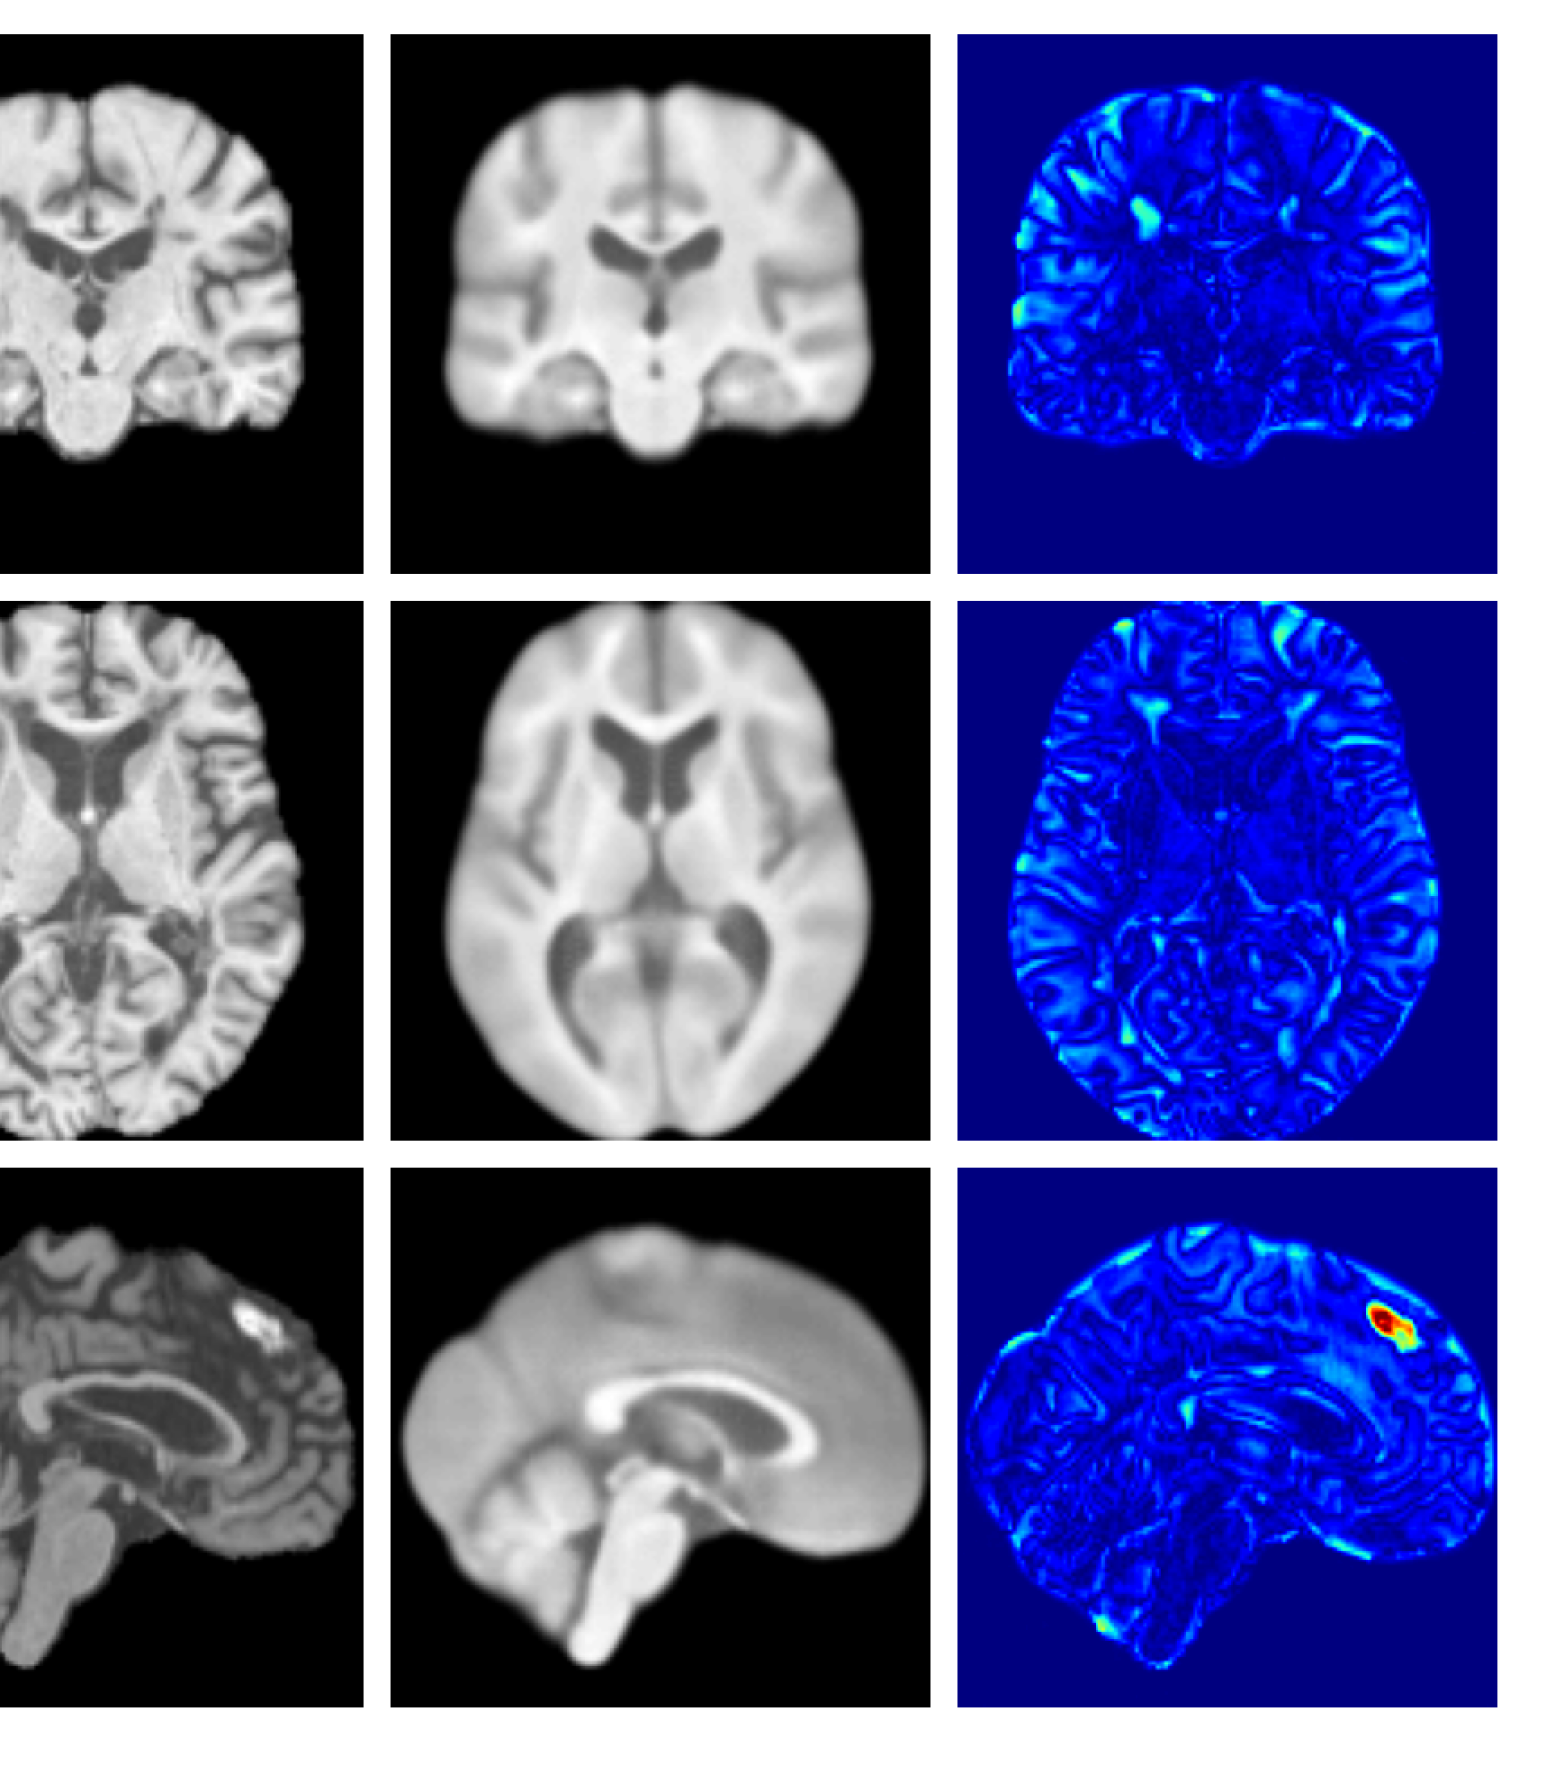

Figure 9: Enlarged example reconstructions and anomaly maps for a sample from the disease cohort of the XXXH dataset. The lesion region is indicated in the original image by the red box.

Figures 8 and 9 are enlarged versions of Figures 3 and 4 respectively, with the latter now including results from all compared methods. Figure 10 provides example reconstructions and anomaly maps for an AD subject from the ADNI disease cohort.